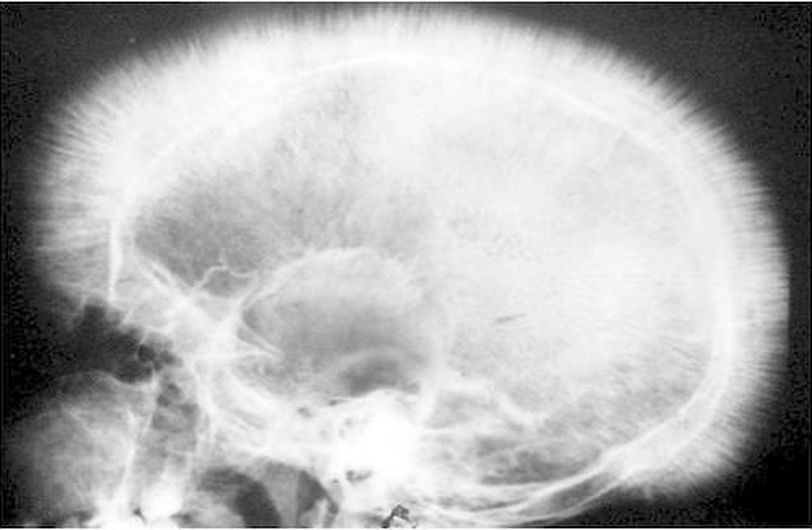

The hair on end sign refers to a radiographic appearance of the diploic space of the skull vault which results from a thickening of trabeculae as the diploic space expands. These trabeculae are perpendicular in orientation, interspersed by radiolucent marrow hyperplasia along with skull vault. This appearance of skull is also known as crew cut. This is classically seen in diseases which require increased erythropoiesis. These diseases can be remembered by mnemonic HI NEST H= Hereditary Spherocytosis I= Iron deficiency anemia N= Neuroblastoma E=Enzyme Deficiency (G6PD Deficiency which leads to hemolytic anemia S= Sickle cell anemia T= Thalassaemia Major Apart from Neuroblastoma, all hyperplasia are caused due to increased erythropoiesis to compete the red cell demand Reference:https://radiopaedia.org/articles/hair-on-end-sign-mnemonic Picture:https://www.stepwards.com/?page_id=877